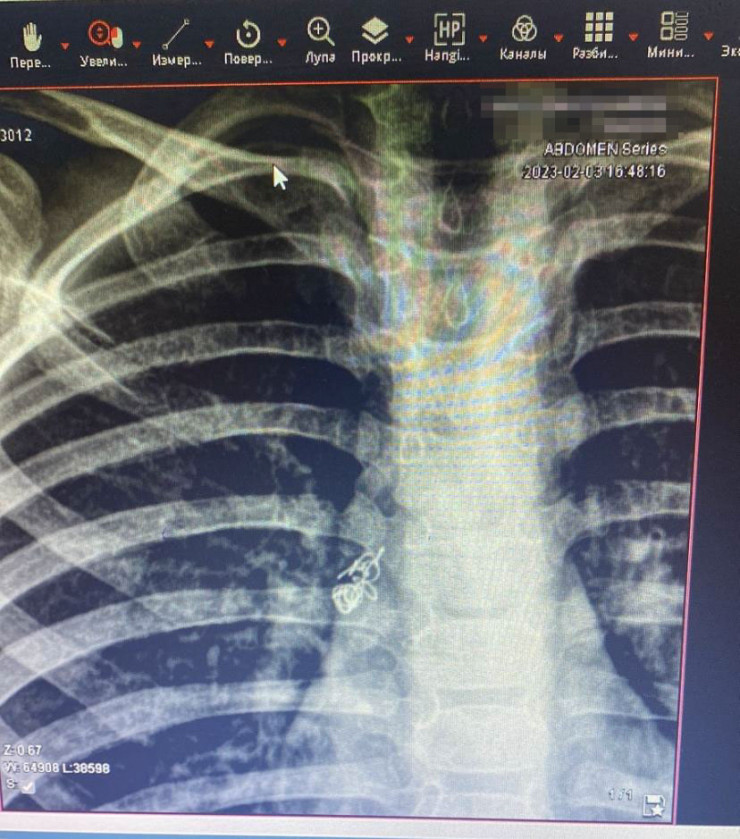

Алматинские врачи спасли ребенка, проглотившего пружинку от ручки Фото предоставлено пресс-службой ДГКБ №2 Алматы

"Ребенок осмотрен специалистами, проведена рентгенография грудной клетки. На рентгенограмме выявили инородное тело правого бронха. Он был госпитализирован, проведена подготовка к манипуляции. Под общим наркозом проведена жесткая трахебронхоскопия. Под визуальным контролем инородное тело (пружинка) обнаружено в правом главном бронхе", - сообщили в пресс-службе ДГКБ № 2.

Специальным зажимом "крокодил" пружина была удалена. Ребенка выписали из больницы через четыре дня.